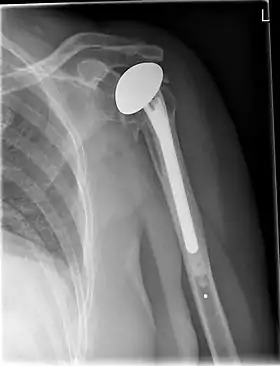

Shoulder replacement is a surgical procedure in which all or part of the glenohumeral joint is replaced by a prosthetic implant. Such joint replacement surgery generally is conducted to relieve arthritis pain or fix severe physical joint damage.[1]

Various materials can be used to make prostheses, however the majority consist of a metal ball that rotates within a polyethylene (plastic) socket. The metal ball takes the place of the patient's humeral head and is anchored via a stem, which is inserted down the shaft of the humerus. The plastic socket is placed over the patient's glenoid and is typically secured to the surrounding bone via cement.[8]